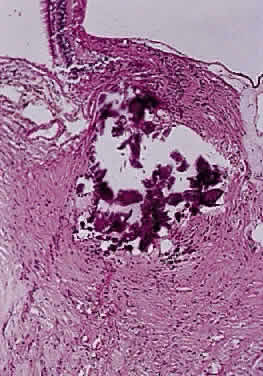

Histologically confirmed metastatic tumors of the optic nerve are uncommon and usually are associated with widespread metastatic disease (Figs. 48 and 49). In only about 1% of cases is the optic nerve predominantly involved.60 The two most common primary sources are breast and lung. Isolated metastasis to the optic nerve is rare; fewer than 20 cases are reported.61–63 Visual disturbance often accompanies meningeal carcinomatosis, typically presenting as rapid visual loss occurring late in the course of the disease. Leukemia and lymphoma may also involve the optic nerve. The frequency with which this is occurring may be increasing because patients survive longer as a result of more effective therapy. Optic nerve involvement by medulloblastoma has also been described.64

Fig. 48. Thickened meninges due to metastases from primary melanoma of the skin (cross-section hematoxylin and eosin staining).

Fig. 49. Amelanotic melanoma cells from primary melanoma of the skin have caused thickening of the meninges (higher power of Fig. 48; hematoxylin and eosin staining).